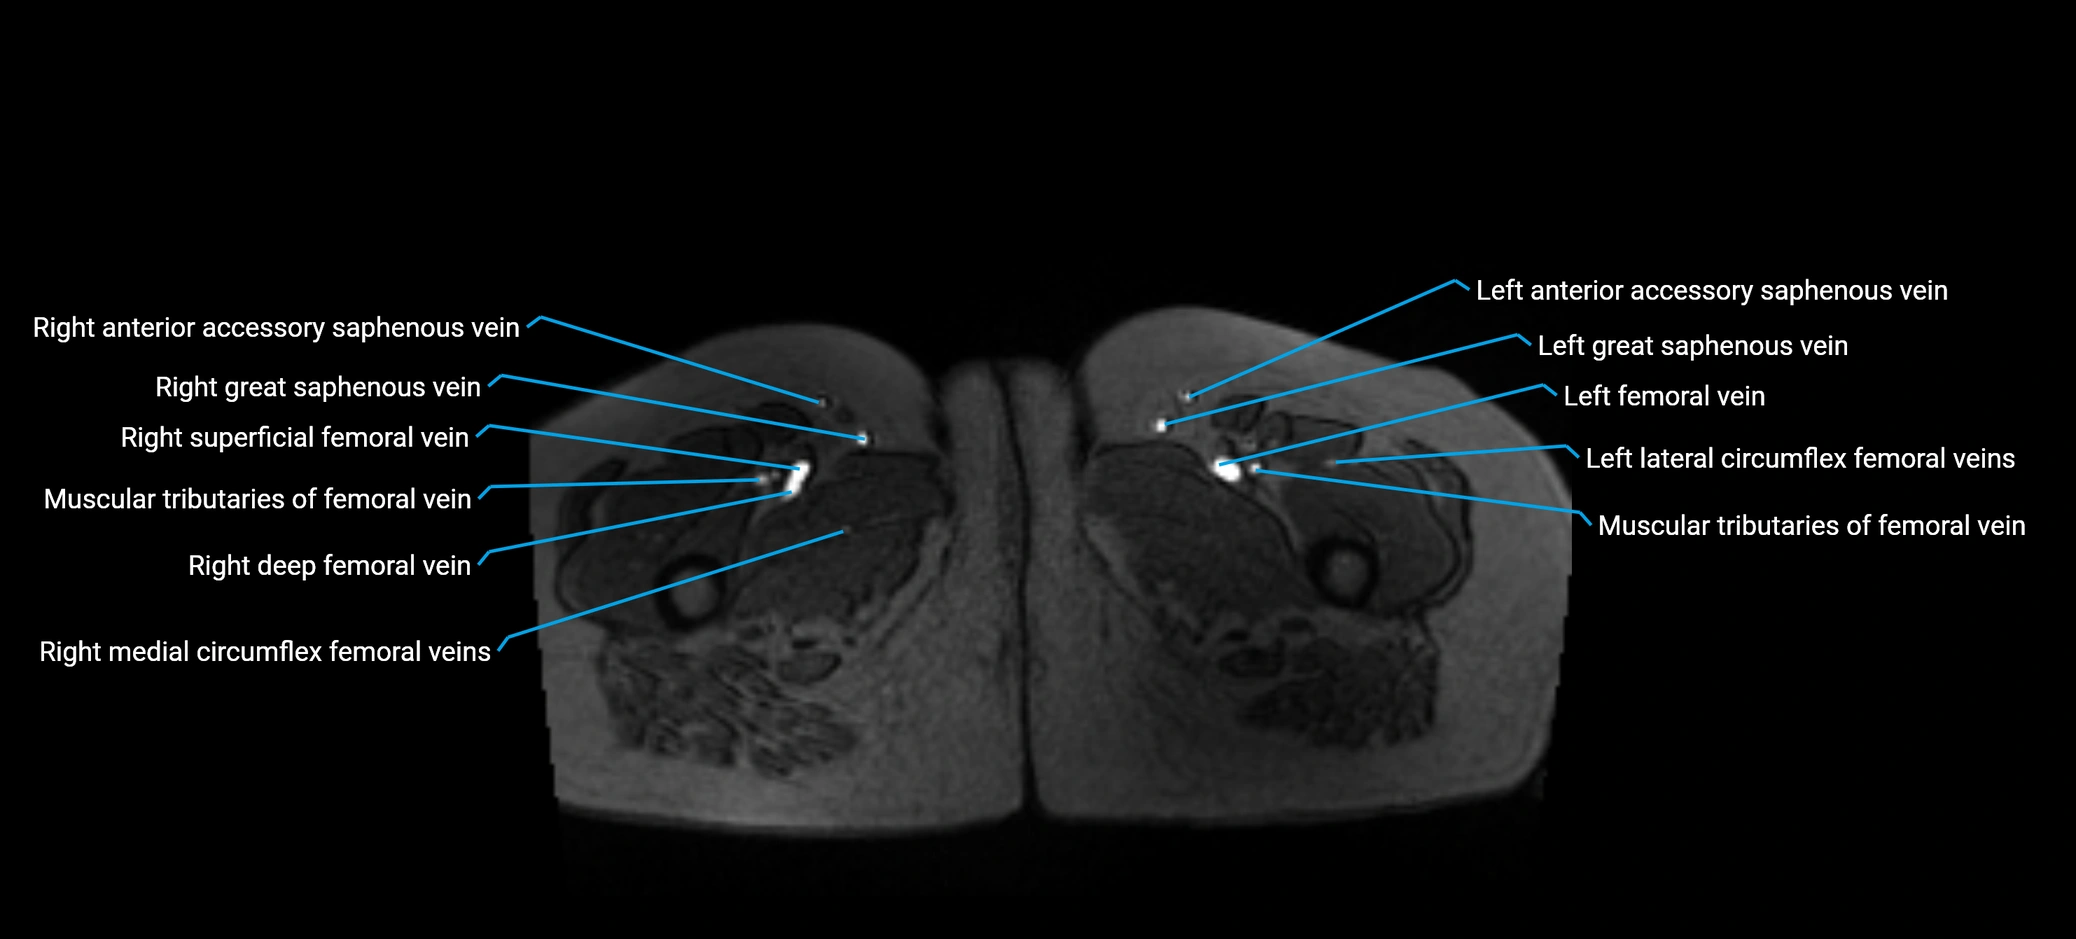

MRI image

image